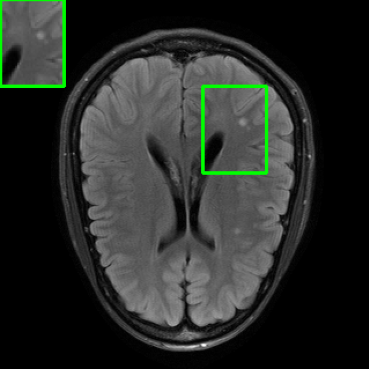

Results for the DIDN-based Reconstructor: To demonstrate adaptability to different network architectures, Table II compares reconstruction performance on the test set with the DIDN denoiser-based MoDL architecture. Average PSNR values with LONDN-MRI are compared to those with networks trained globally at different training set sizes. We ran only iteration of LONDN-MRI, where the reconstruction with a pre-trained (global) network was used to find neighbors. PSNR values for the oracle LONDN-MRI reconstructor are also shown. The overall performances with the DIDN-based architectures are better than with the UNet-based unrolled networks. The PSNRs for LONDN-MRI are consistently and similarly better than for the globally trained network across the different training set sizes considered, indicating potential for LONDN-MRI in improving state-of-the-art models. Fig. 6 visually compares reconstructions and reconstruction errors (in zoomed in region) for different methods. We can see that the LONDN reconstructors capture the original image features more sharply and accurately than the globally learned reconstruction.

| Ground Truth | Global | LONDN-MRI | Oracle |

| (1 iteration) | |||

![]() |

| PSNR = dB | PSNR = 34.15 dB | PSNR = 34.46 dB | PSNR = 34.54 dB |